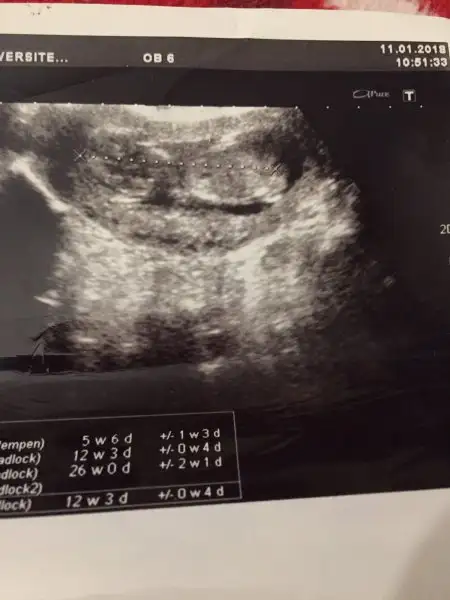

Kızlar ilk oğlumun usg lerini buldum fikir olsun diye paylaşıyorum tüm yüz hatları ağız dudak çene göz çukurları bile belli gerçekten erkek bebekler daha belirgin oluyor sanırım yinede usg cihazından olabilir bilmiyorum bu usg 9 sene öncesi